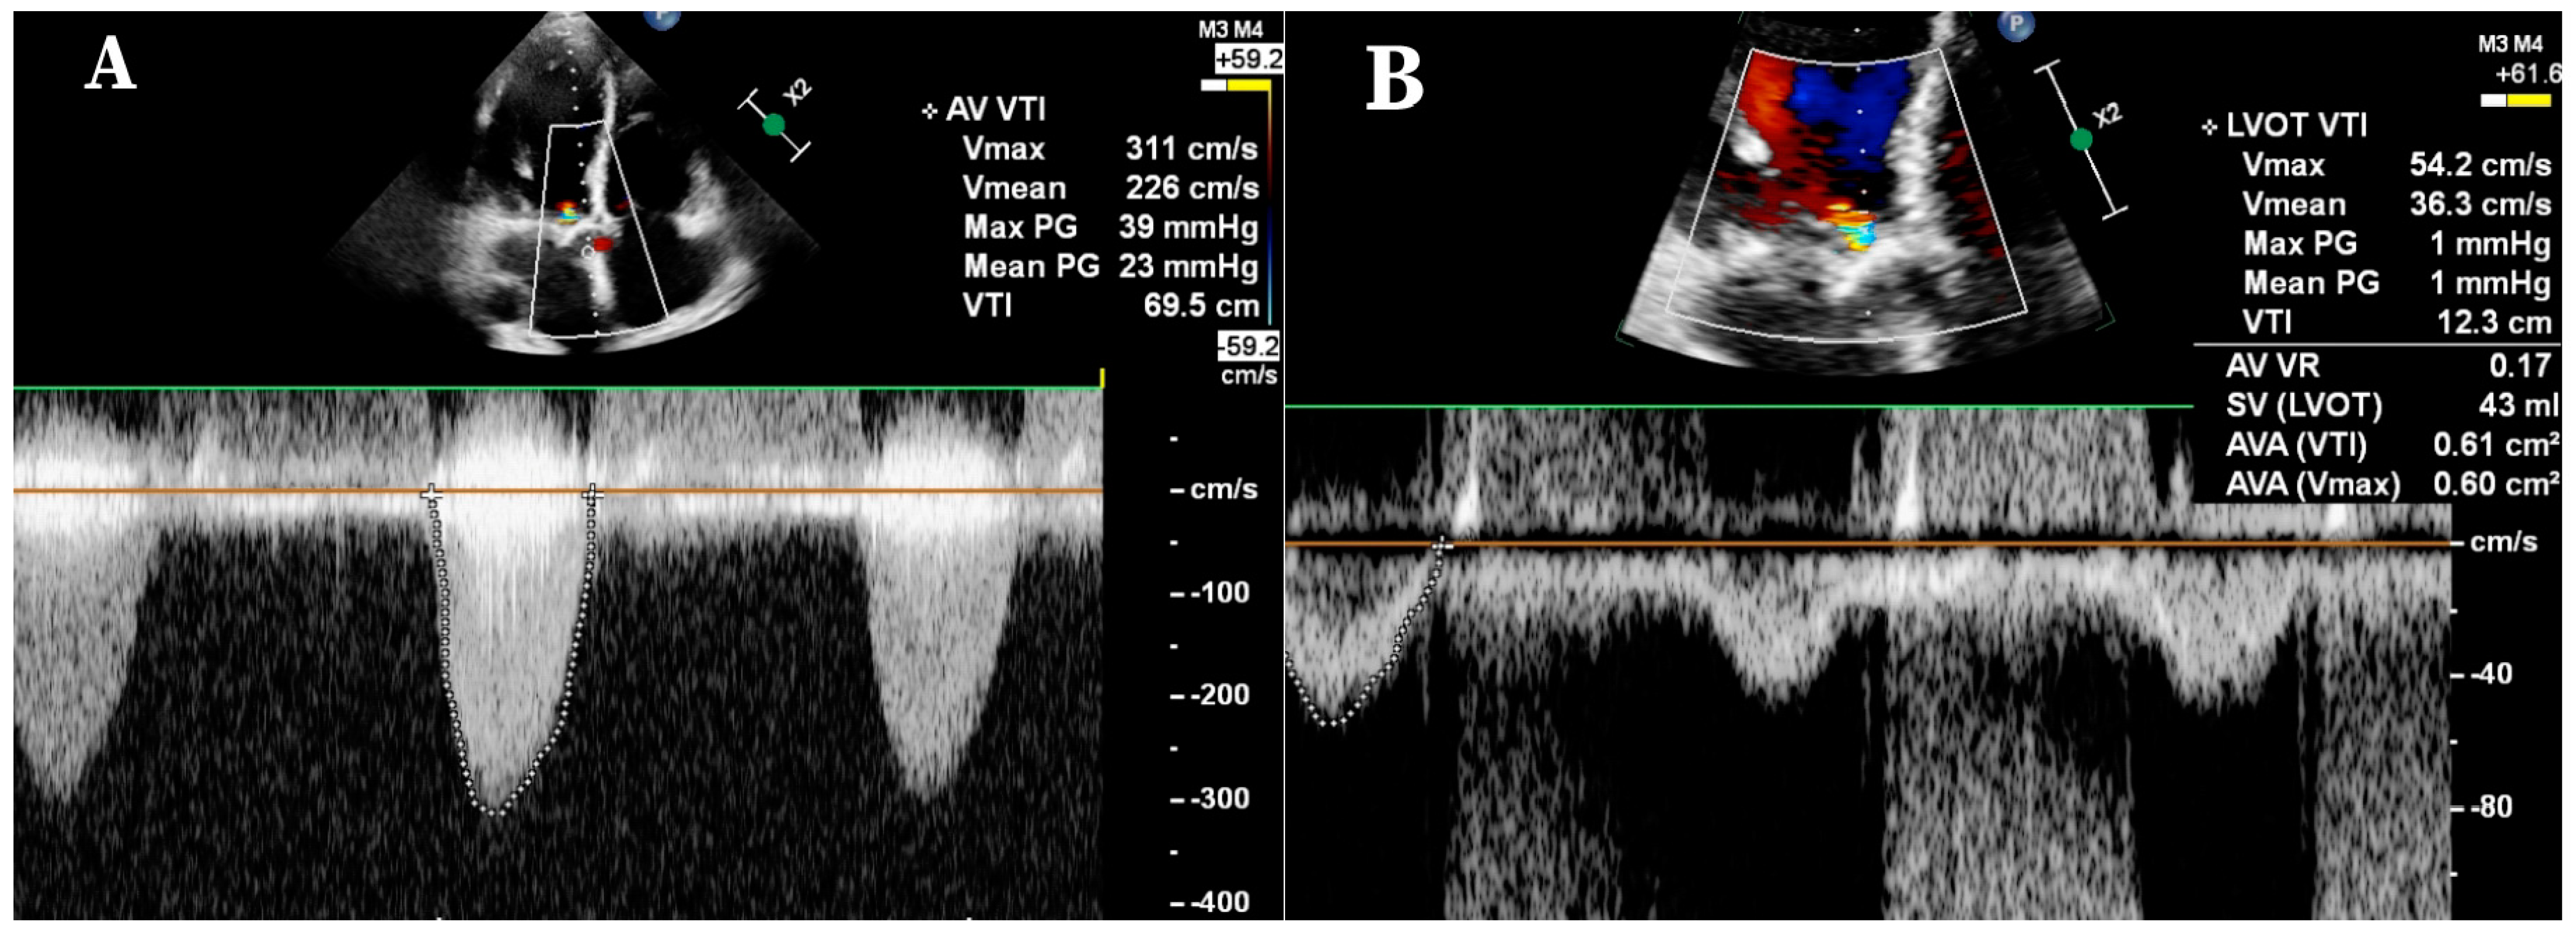

2. Methods

- Possible correlation between the ECHO and the CCTA density parameters in SAS patients.